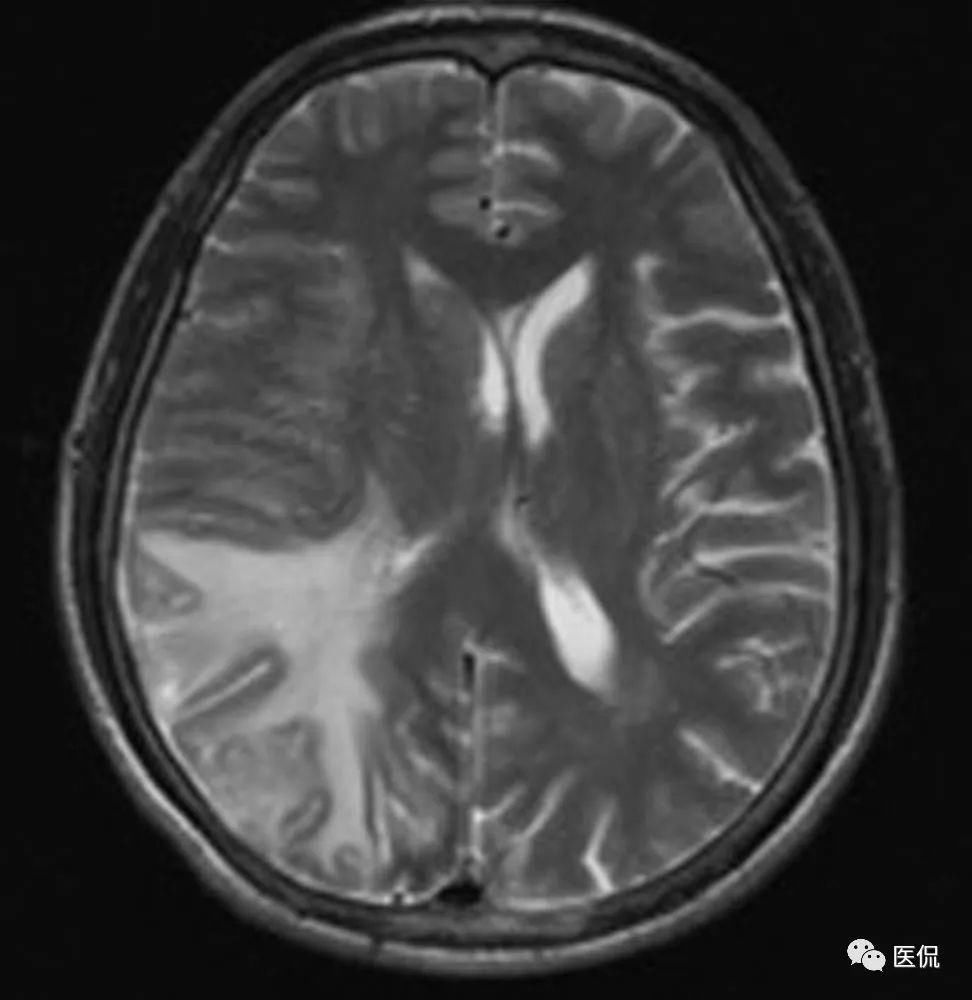

头痛头晕,MRI特点为右侧顶颞枕部脑膜强化、以